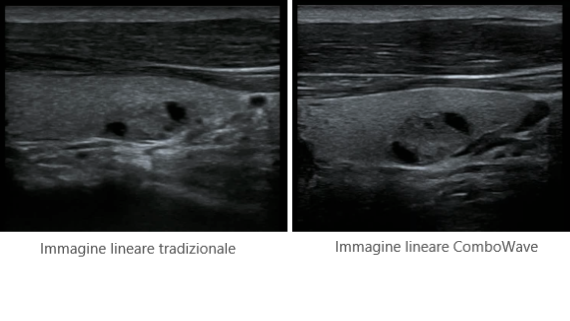

X-Insight ├© una soluzione completa studiata per offrire la migliore qualit├Ā diagnostica.

La nuova soluzione di Mindray ├© la traduzione pratica delle esigenze quotidiane dei clienti in soluzioni cliniche, il tutto con tecnologie ad ultrasuoni all'avanguardia ed in continua evoluzione.

Progettato per rispondere al meglio alle esigenze del cliente, DC-60 Exp con X-Insight ├© studiato per offrire un'efficienza elevata nel campo dell'imaging di precisione, grazie a una chiarezza immediata (eXpress Clarity), allŌĆÖeccezionale intelligenza (eXceptional Intelligence), oltre a vantare una lunghissima esperienza (eXceeding Experience).